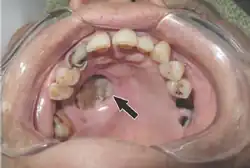

-

Mucormycosis in eye -

Tissue destruction of inside upper mouth -